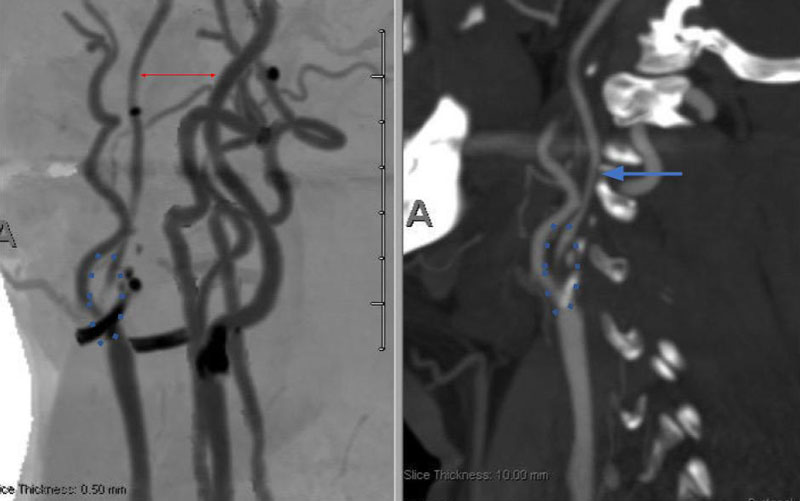

Catheter cerebral angiography was then performed which demonstrated the 99% stenosis with distal vascular collapse and extension of the plaque superiorly into the mid third of the cervical right ICA (Figure 4). Interrogation for collaterals from the left ICA and posterior circulations demonstrated very small and minimal contributions from the anterior communicating artery and posterior communicating artery of the Circle of Willis.

Figure 4. A) DS Angiogram demonstrates severity and extent of plaque to C2-3 level (blue). B) And marked delay of ICA perfusion (yellow) relative to ECA branches (green).